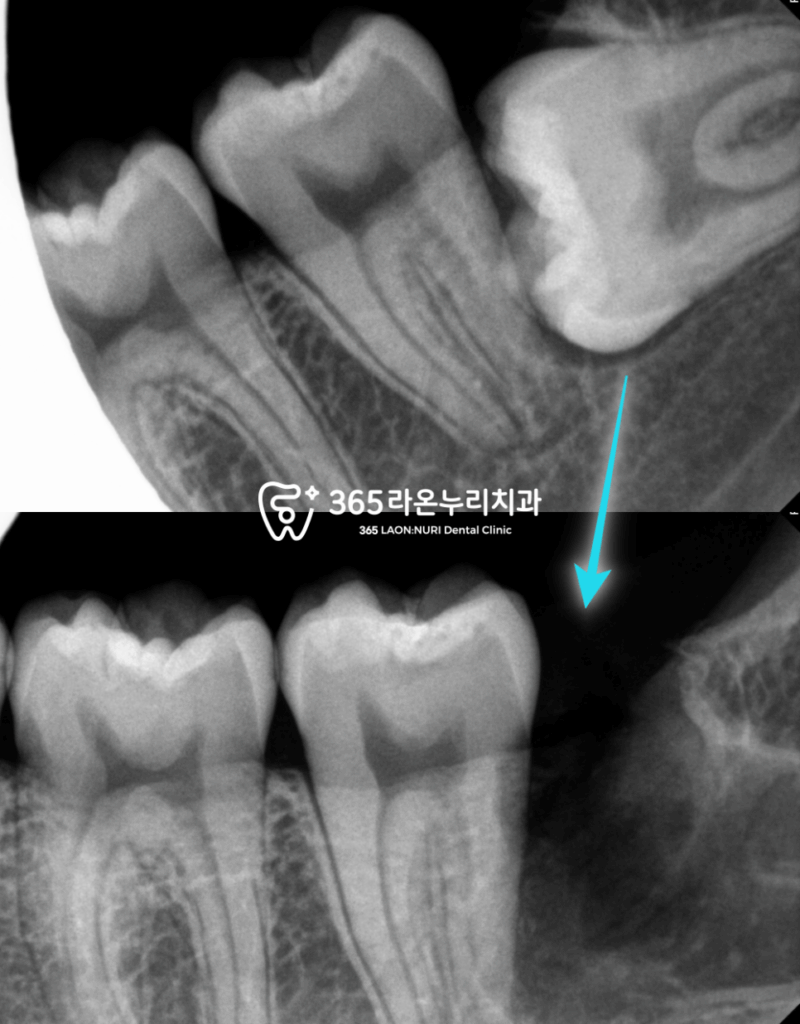

동탄동 치과 방사선 사진을 같이 보면

제 3대구치가 있습니다.

그리고 기울어져 있는 뿌리끝을 보면

턱뼈의 형태를 따라

크게 가로질러 주행하고 있는

신경관이 확인됩니다.

이 신경관을 잘못 건드리게 되면

신경마비 증세(부작용)이 올 수 있으므로

수술 계획을 세울 때

매우 신중하게 결정해야 됩니다.

모두 끝난 후 촬영한 방사선 사진에서

사랑니가 모두 깔끔하게

발치된 것을 동탄동 치과 에서

확인할 수 있었습니다.